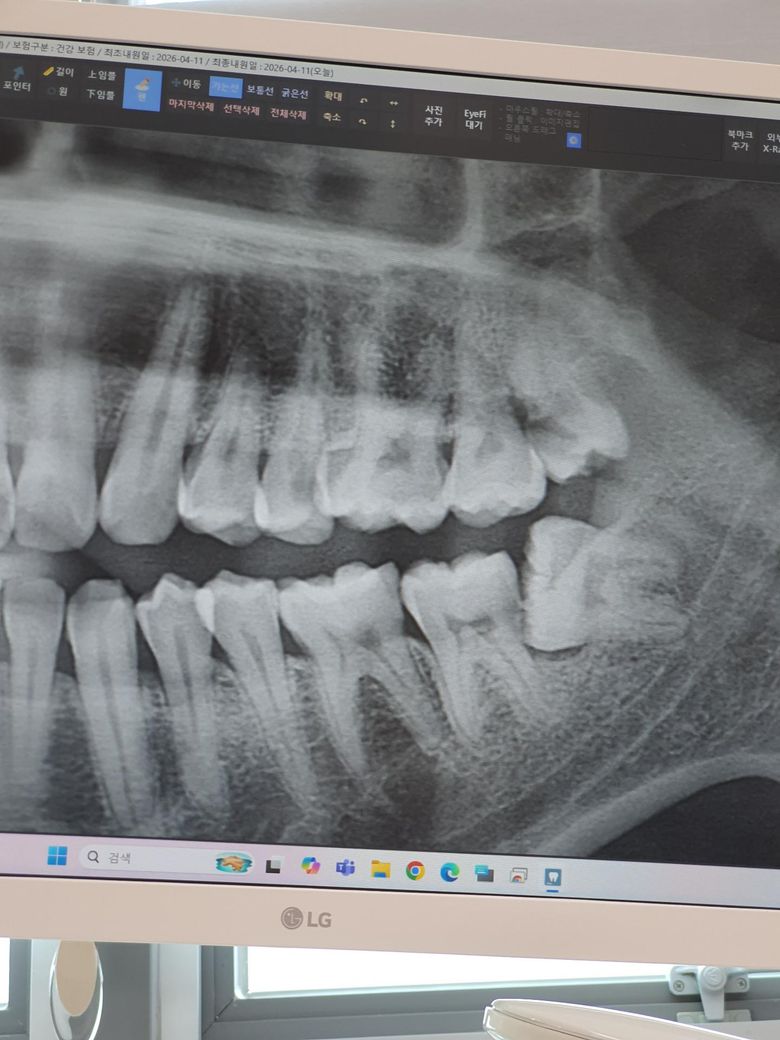

사랑니 옆 어금니가 딱딱한 걸 씹으면 아파서 갔더니 엑스레이만 보고 충치라고 말하고 크라운을 바로 얘기하던데 어떻게 보이나요..

사진으로 봤을 때에는 우식 의심되는 상황이며 사랑니 발치 후 해당 부위에 대한 재평가 요합니다. 사랑니는 발치하시는게 맞는 상황으로 보입니다. 방치시에는 앞에있는 어금니를 못쓰게 되는 상황 올 수 있으므로 미루지마시고 치료 받으시기를 바랍니다.

저건 빼고 직접 봐야합니다 사랑니가 있는 상태에서 엑스레이 찍으면 왜곡때문에 대부분 저렇게 나옵니다